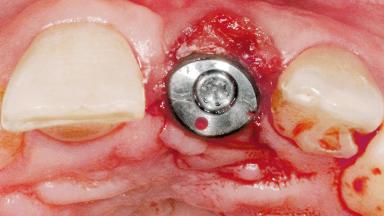

Late Flapless Placement of an Implant in a Maxillary Left Central Incisor Site

A 39-year-old male patient presented with a chief complaint of discomfort and gingival discoloration around his maxillary left central incisor. He was in good general health and was a non-smoker. His past dental history was significant because of the traumatic fracture of tooth 21 in a sporting accident at age 13. Initial dental treatment included endodontic therapy and a full-coverage restoration. The patient became symptomatic 5 years later, when structural failure of the tooth resulted in the dislodgment of the crown. Endodontic retreatment, apical surgery, and post-and-core restoration were performed.